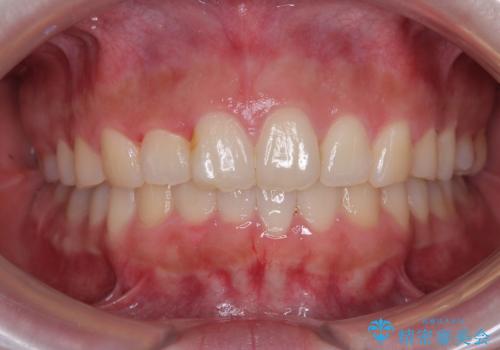

後戻りの再矯正 ワイヤー装置でデコボコと隙間を改善